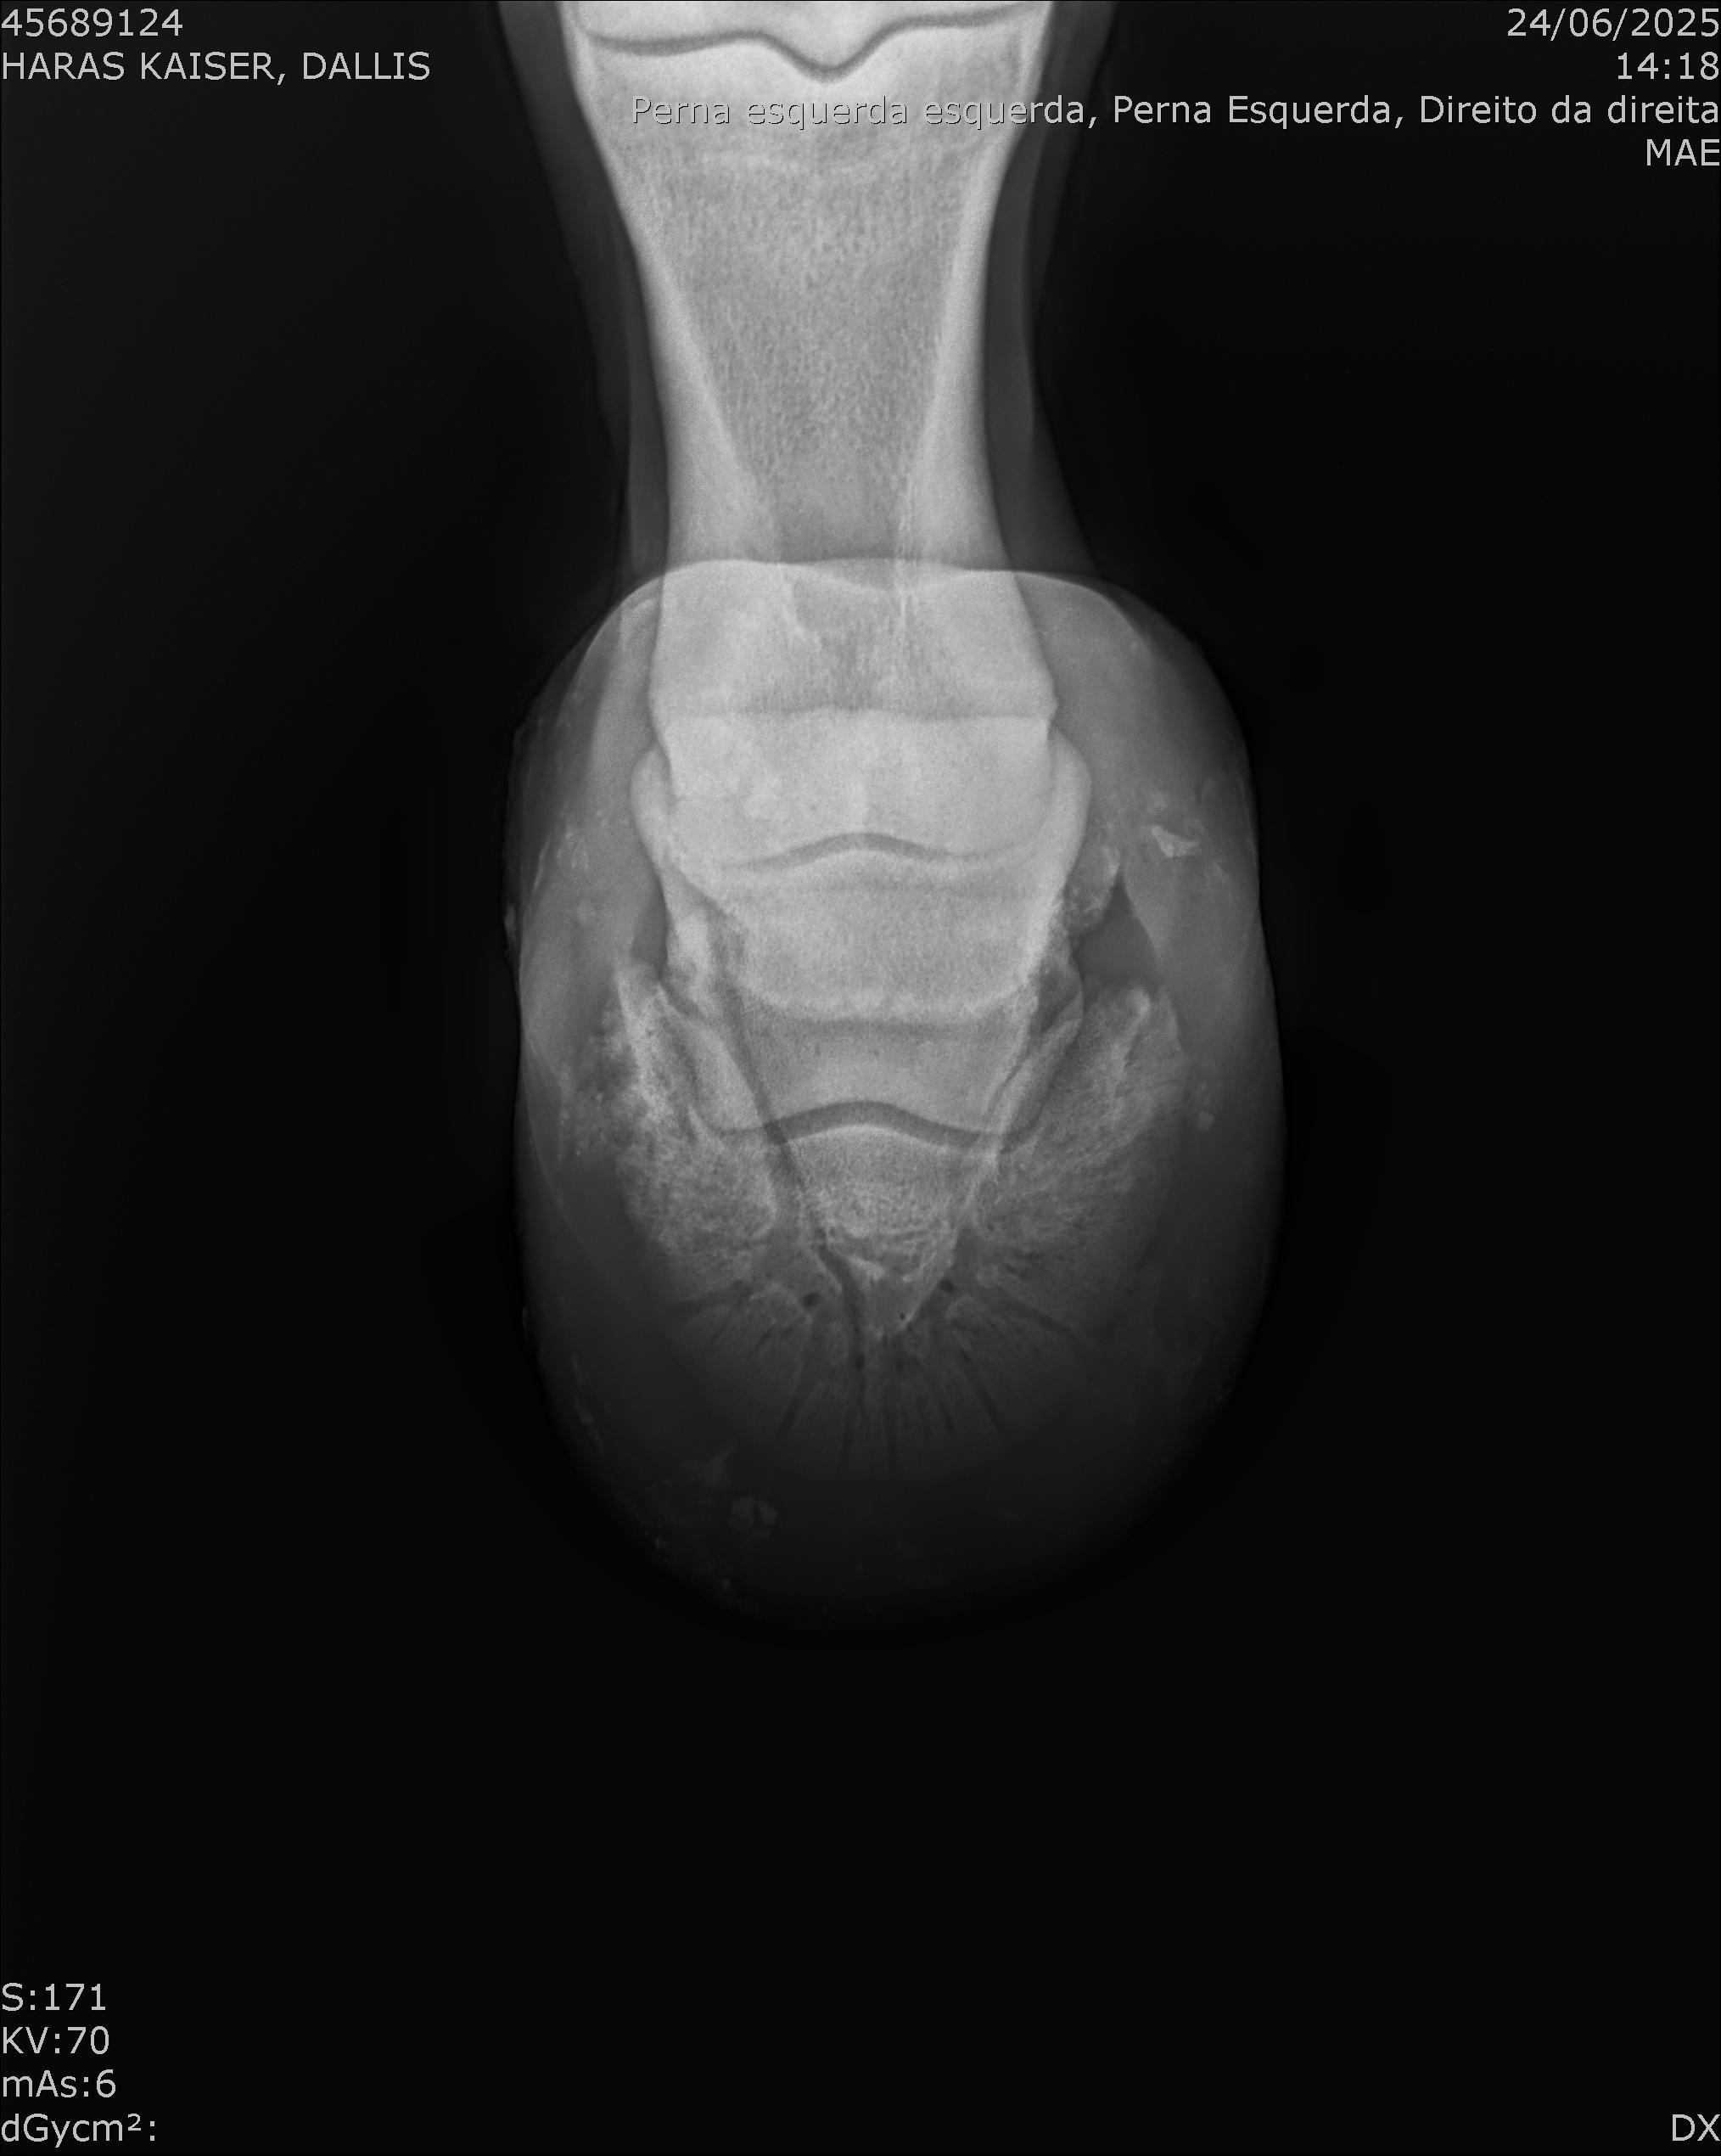

:: RAIOS-X DO LOTE